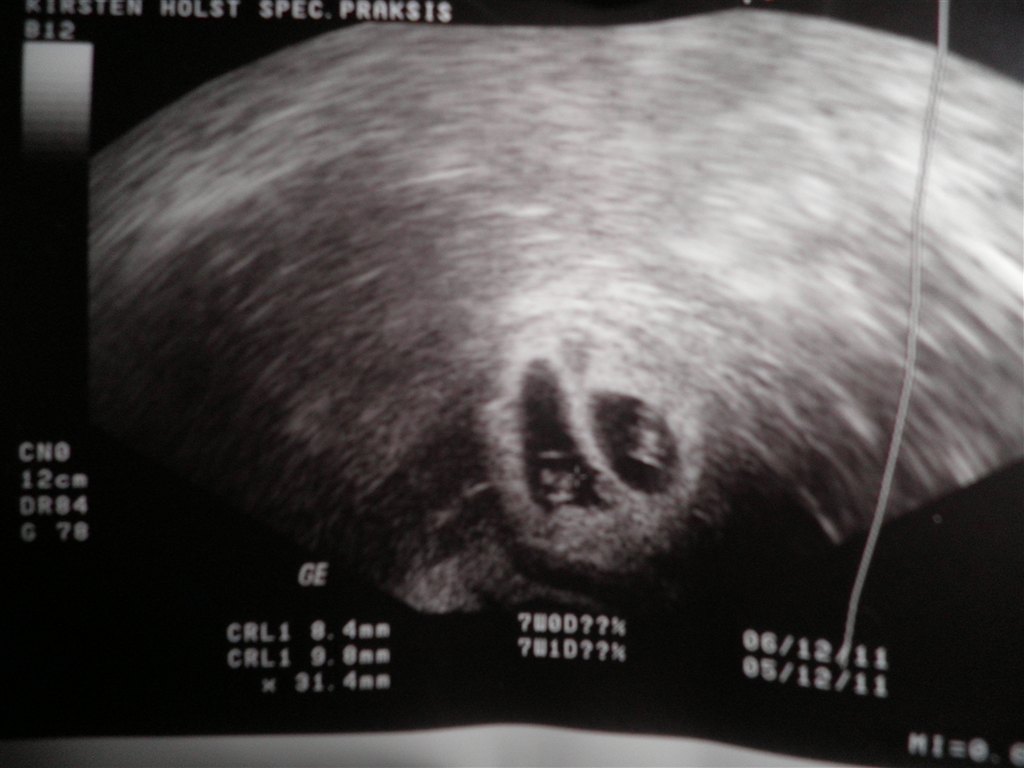

Tillykke, det ligner godt nok meget det billed jeg har fra min tryghedsscanning

Glæder mig til, at høre mere. Spørg endelig, hvis det er tveæggende (som jeg tror, synes det ligner meget min scanning) så kender jeg rimelig godt til graviditets forløbet.

Bonus info, er det tveæggende, så er abort risikoen mindre